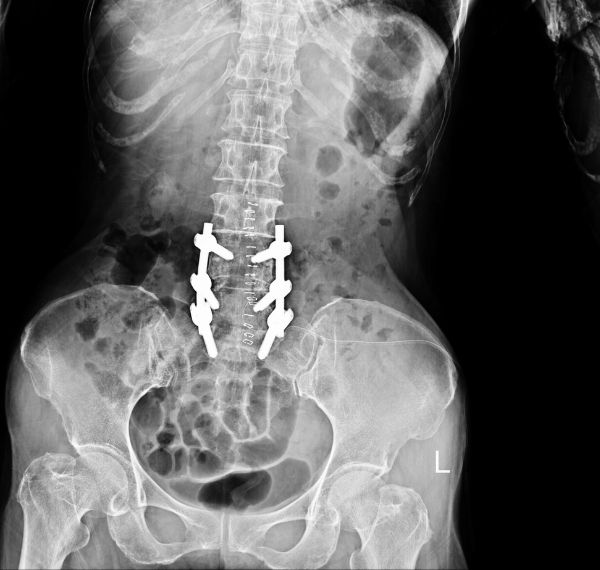

Spine Surgery (Discectomy/Laminectomy)

Surgical procedures to relieve pressure on spinal nerves.

Deformity Correction Surgery

Realigns bones or joints due to congenital or traumatic deformities.